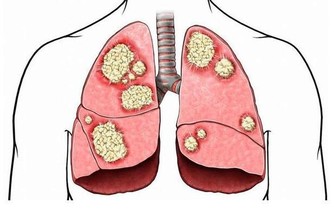

升結腸、橫結腸的癌症:症狀更難察覺。這些部位與小腸相連,小腸運來的糞便還處於液態,

即使此處有癌腫出血,出血量也不會太多,肉眼很難觀察到。

但如果出血時間長,會出現貧血,很多人都是出現貧血才發現大腸癌的。

所以,貧血是大腸癌的共同症狀。